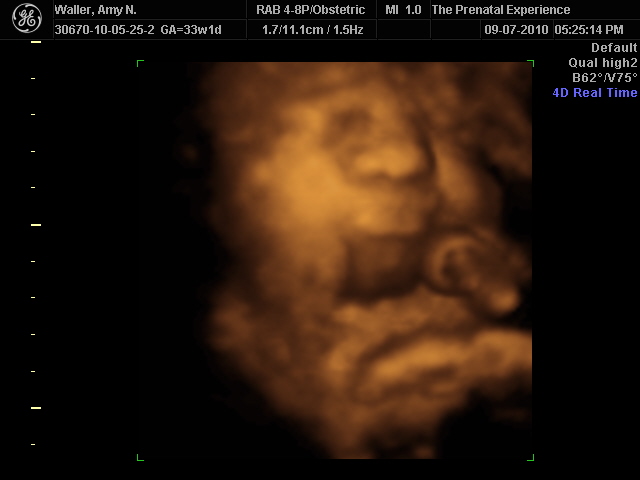

I mean, look at those chubby little cheeks and that pouty bottom lip (I don't have a clue where she got that from!). How can I not be anxious to stare at that everyday!?!